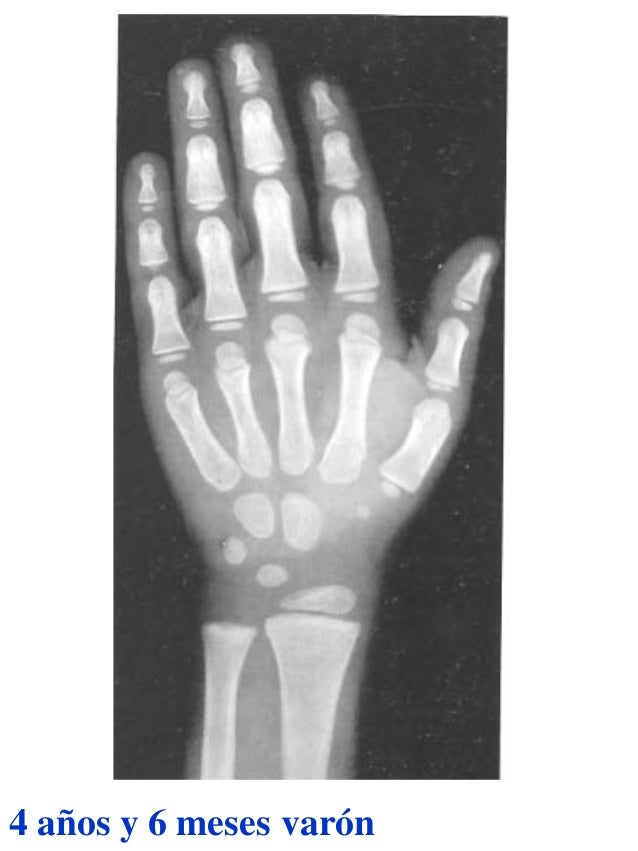

Figura 2 Imágenes de radiografías de mano y muñeca izquierda del

Figura 2 Imágenes de radiografías de mano y muñeca izquierda del Tablas De Greulich Y Pyle Edad Osea The greulich and pyle atlas is used to estimate the age of children and adolescents. El método de greulich y pyle(1) es un método simple de valoración de la edad ósea en pacientes pediátricos. El diagnóstico y la clasificación se basan en el examen físico, el análisis del crecimiento, la maduración ósea, la ecografía de útero y gónadas, y los. Tablas De Greulich Y Pyle Edad Osea.